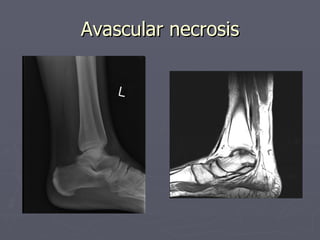

Avascular necrosis

• 70.